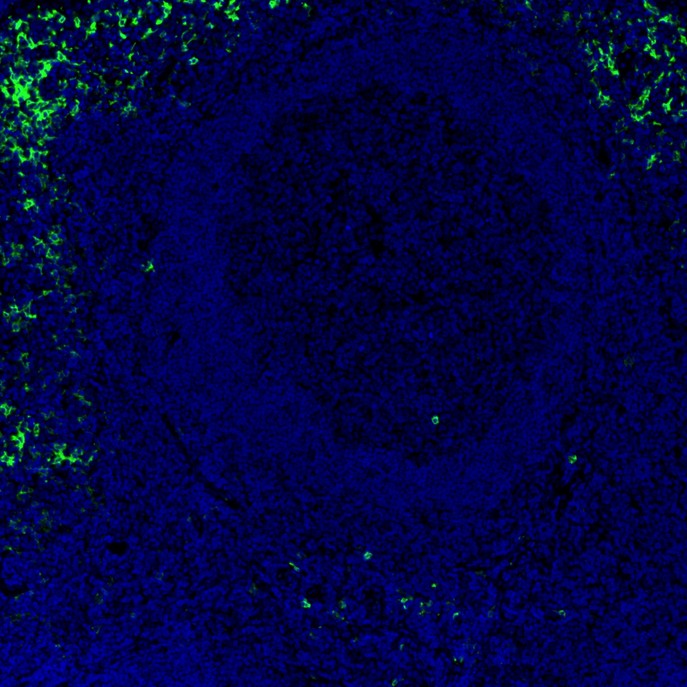

CD16 Recombinant Rabbit Monoclonal Antibody [PD00-12]

IF-Tissue